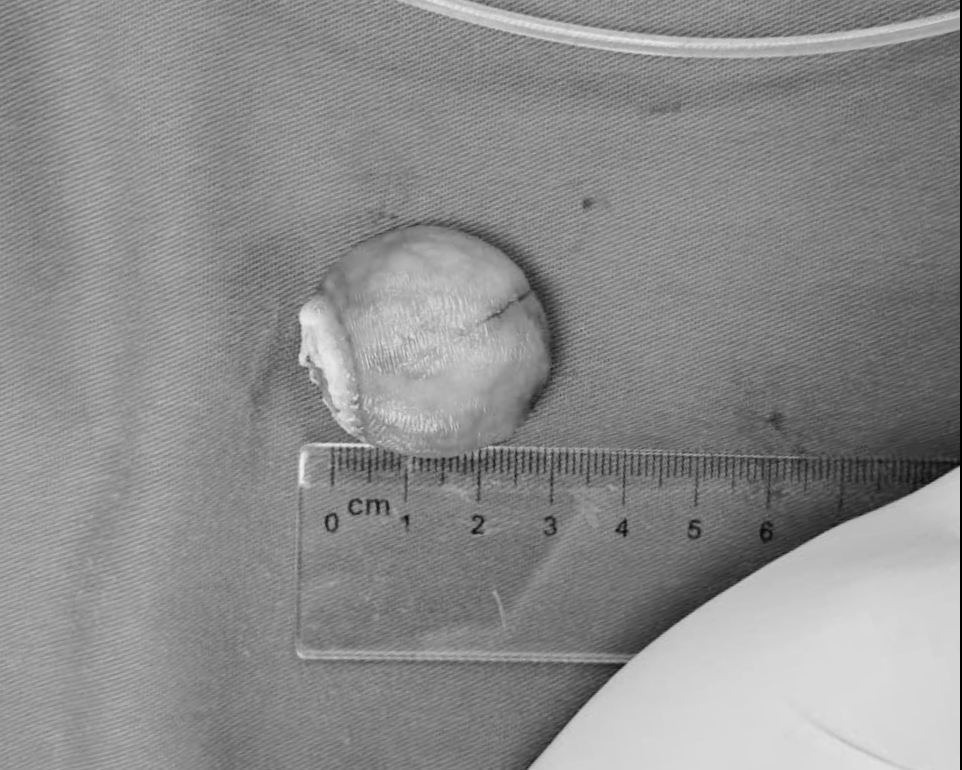

Quá trình nội soi tiêu hoá các bác sĩ phát hiện bệnh nhân có khối u dưới niêm mạc đại tràng với kích thước khoảng 3 cm, chiếm gần hết đại tràng, gây cản trở nhu động ruột – nguyên nhân trực tiếp khiến bệnh nhân gặp tình trạng chướng bụng, khó đi ngoài.

Ngay sau khi phát hiện, các bác sĩ của Bệnh viện TNH Việt Yên đã tiến hành hội chẩn và chỉ định cắt toàn khối qua nội soi tiêu hoá. Khối u có mật độ cứng, nằm dưới lớp niêm mạc, thuộc nhóm tổn thương có khả năng lành tính hoặc ác tính tùy theo bản chất mô học. Khối u sau đó được gửi đi làm xét nghiệm giải phẫu bệnh (mô bệnh học) hay còn gọi sinh thiết, kết quả xét nghiệm là u lành tính và diện cắt không còn u.